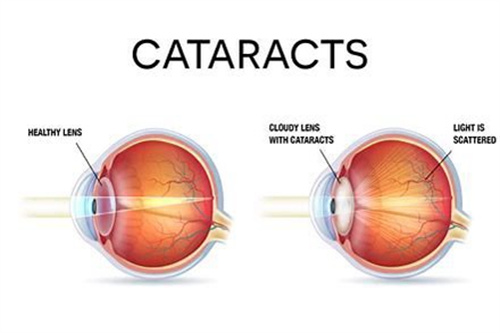

在眼科医疗领域,德国制造常被视为品质与技术的代名词。作为德国本土深耕眼科器械的品牌,德国人类光学(Human Optics)凭借其人工晶体产品,在白内障、老花眼等视力矫正领域占据重要地位。